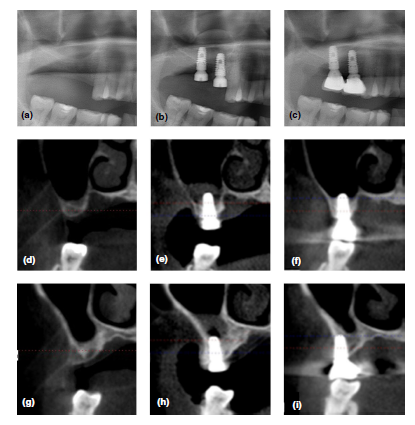

Radiologic comparative analysis between saline and plateletrich fibrin filling after hydraulic transcrestal sinus lifting without adjunctive bone graft: A randomized controlled trial

13 de agosto de 2020 · Yong-Seok Cho, Kyung-Gyun Hwang, Sang Ho Jun, Marco Tallarico, Amy M. Kwon, Chang-Joo Park

AbstractObjectives: To evaluate implant survival rate, any complications, and changes in residualalveolar bone height (RABH) using saline or platelet-rich fibrin (PRF) filling afterhydraulic transcrestal sinus lifting.M…